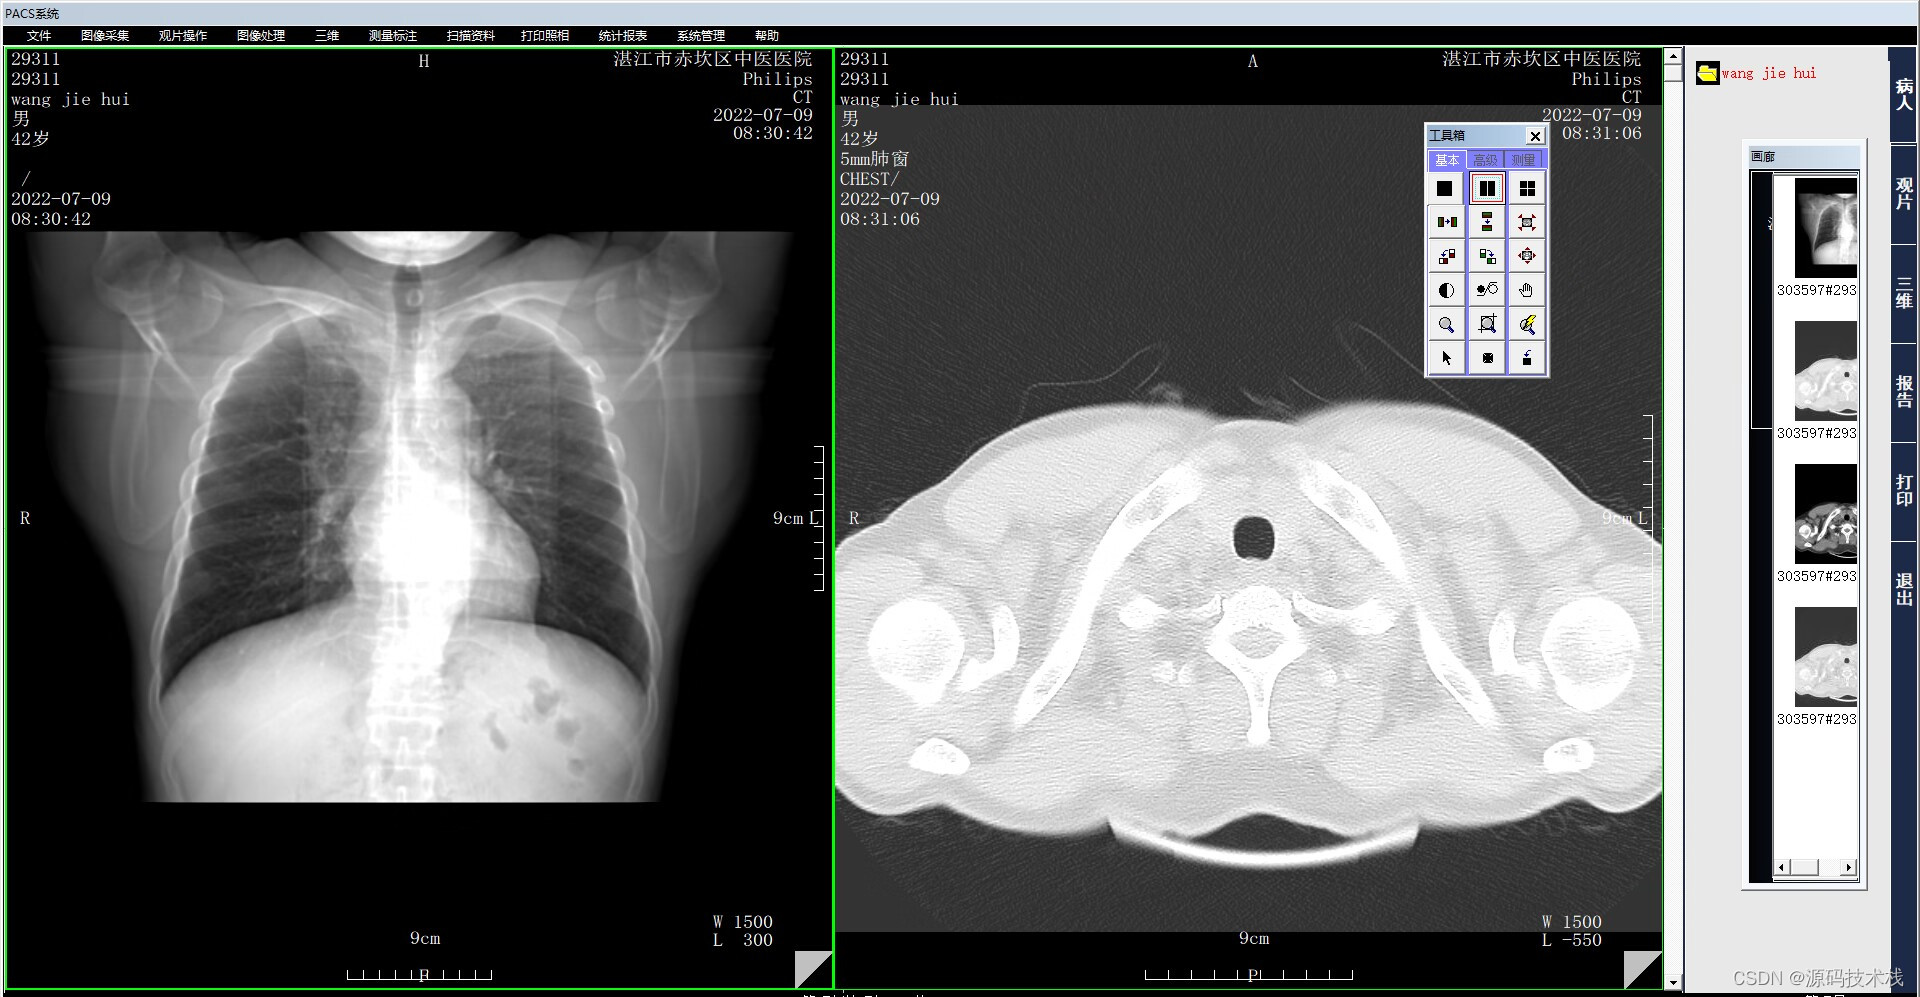

医学影像PACS系统源码: 三维重建基本后处理方法的介绍和说明

PACS源码,有演示,有文档,有源码,项目源码,私信博主了解更多PACS三维重建功能!

CT三维重建主要包含以下基本后处理方法: